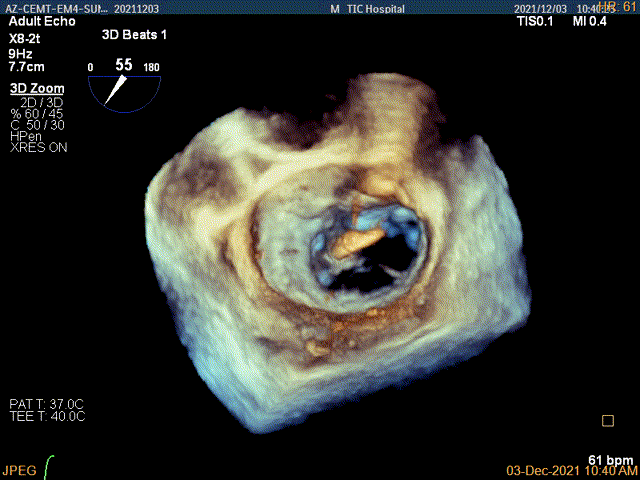

3D视图菲薄的卵圆窝,穿刺点位近似于3点位

3D视图下大鞘位置及长度测量

3D视图下到达目标位置

3D视图下开夹子旋转使得clip的两个arm与MV对合线垂直